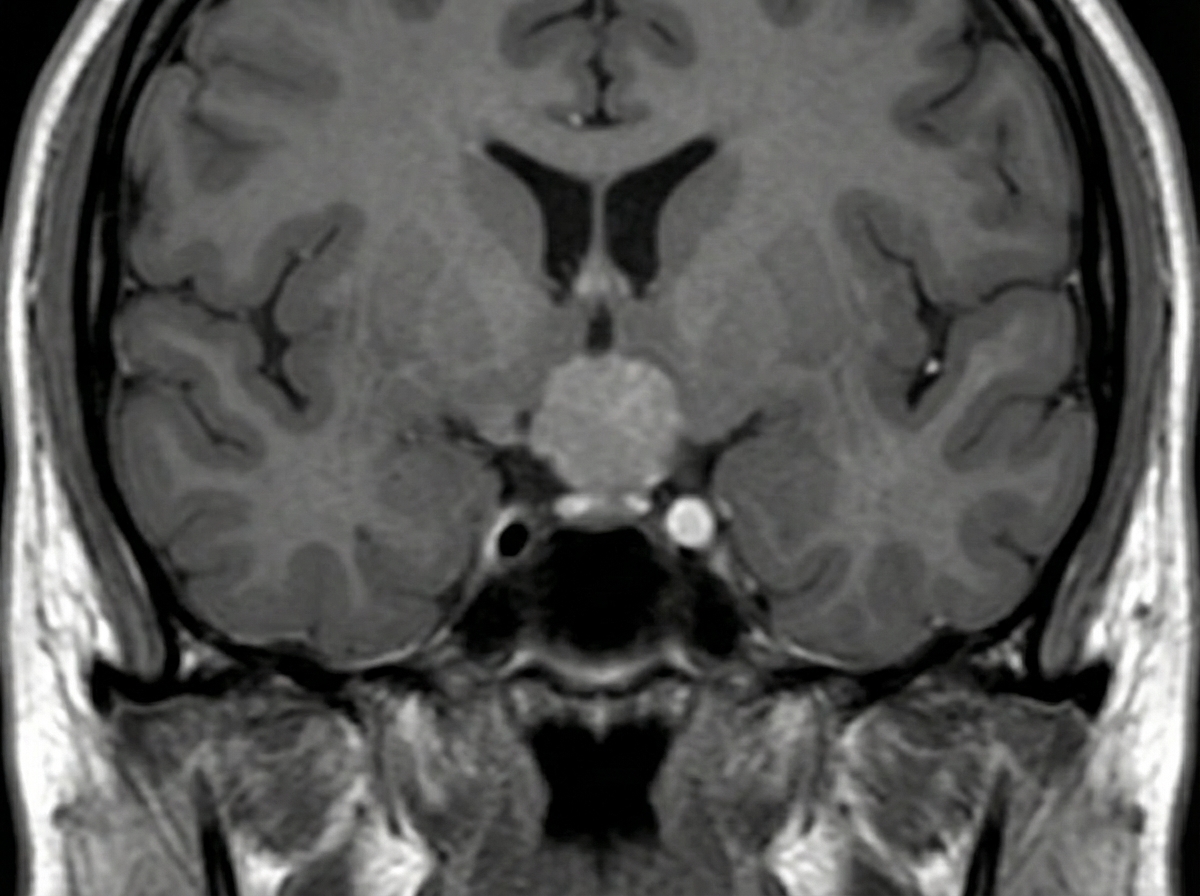

A 34-year-old man presents with a chief complaint of blurring of vision in both eyes and headache for the past six months, accompanied by decreased libido. Examination reveals bitemporal hemianopia. An MRI was performed. What is the most likely diagnosis?

Explanation: ***Pituitary macroadenoma*** - **Bitemporal hemianopia** indicates compression of the **optic chiasm** by a mass >10mm, which is characteristic of macroadenomas causing **mass effect**. - The combination of **headache**, **decreased libido** (hypogonadism), and **visual field defects** forms the classic triad of pituitary macroadenoma. *Pituitary microadenoma* - **Microadenomas** are <10mm in size and typically do **not cause compression** of surrounding structures like the optic chiasm. - They usually present with **hormonal excess** (prolactinomas, growth hormone excess) rather than **mass effect symptoms** like bitemporal hemianopia. *Meningioma* - **Meningiomas** arise from the **arachnoid mater** and would cause different visual field defects depending on location, not specifically bitemporal hemianopia. - They typically present with **seizures**, **focal neurological deficits**, or **personality changes** rather than endocrine dysfunction like decreased libido. *Hemangioma* - **Hemangiomas** are **vascular malformations** that rarely occur in the sellar region and would not typically cause optic chiasm compression. - They usually present with **hemorrhage** or **seizures** rather than the gradual onset of **visual field defects** and **endocrine symptoms**.